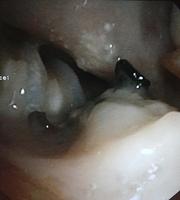

Fistulas

Tracheoesophageal or bronchoesophageal fistula

Tracheomediastinal or bronchomediastinal fistula

Tracheobiliary or bronchobiliary fistula